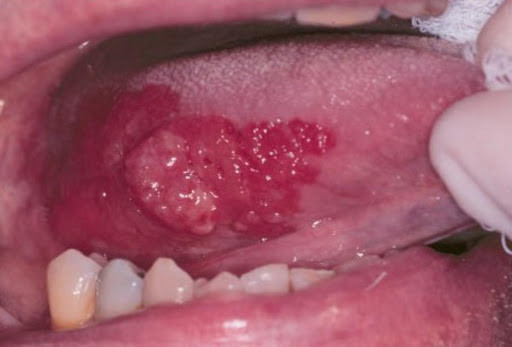

Erythroplakia. This is a red patch that can be both flat or slightly raised. When scraped, it bleeds easily.

A dental professional can perform a thorough soft tissue and head and neck exam to detect possible lesions. Research from Jefferson University Hospitals has found that erythroplakia is generally seen on the tongue or the mouth floor. You can also find lesions in the back of the throat and just behind the last molars.